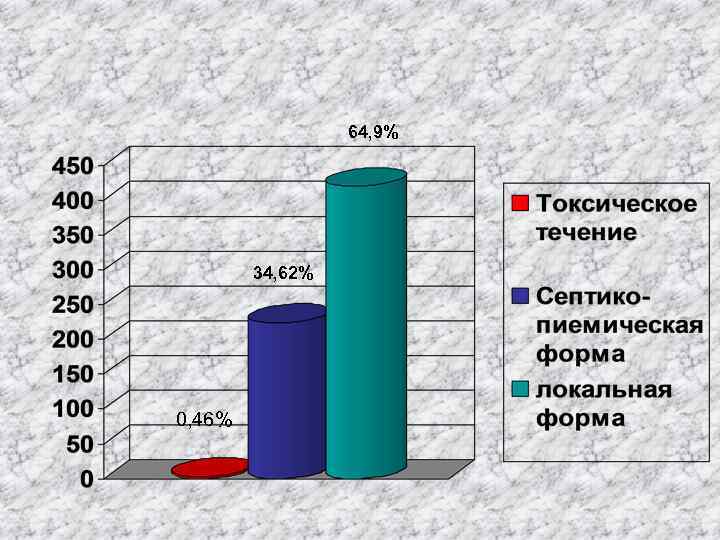

64, 9% 34, 62% 0, 46%

64, 9% 34, 62% 0, 46%